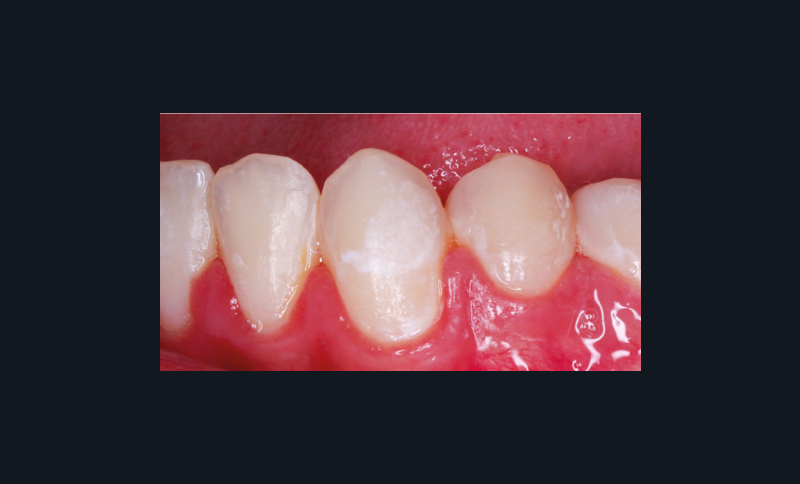

La première phase du cycle correspond à la déminéralisation. Elle se définit comme la fuite de certains éléments minéraux constitutifs (calcium, phosphate) des tissus minéralisés par dissolution acide [7]. Celle-ci provient donc soit de la production d’acides dans le biofilm avec une libération d’ion H+, soit d’une origine intrinsèque ou extrinsèque. Lorsque la solution acide entre en contact avec l’émail, elle diffuse à travers le biofilm. Ce n’est qu’après qu’elle peut interagir directement avec les tissus minéralisés de la dent, et plus précisément avec les cristaux d’hydroxyapatite qui composent l’émail, puis pénétrer dans le gel aqueux qui occupe le réseau des pores de l’émail. Il se produit donc une perturbation des équilibres ioniques au niveau de l’interface tissu dentaire/gel aqueux du biofilm [8].